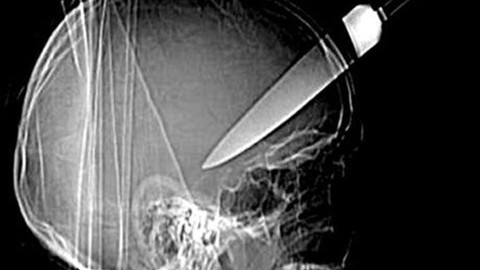

Bu röntgen filmleri görenleri şoke ediyor

Şoke eden röntgen filmleri Galerinin tamamı için tıklayınız Bu röntgen filmleri görenleri şoke ediyor